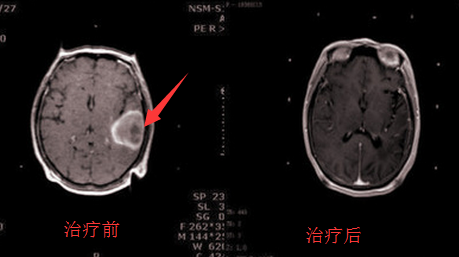

颞叶脑胶质瘤治疗前后对比

临床研究已证实:采用WB-1全身热疗+P53基因治疗,包括头颈部肿瘤、脑胶质瘤、宫颈癌、肺癌、胃癌、肠癌、食道癌、卵巢癌、脂肪肉瘤、横纹肌肉瘤、复发性甲状腺癌和胸腹腔转移癌等。32%的病人肿瘤完全消退(CR),27%的病人肿瘤部分消退(PR),41%病人肿瘤停止生长(SD)。在美国、加拿大、日本和欧洲的30多个医学中心联合化疗或放疗治疗复发性晚期癌症病人,其疗效高于单纯放疗、化疗疗效3倍,没有毒副作用。